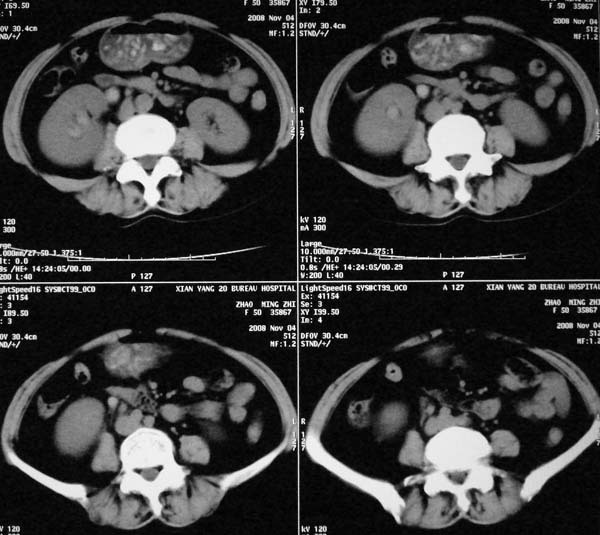

以下是引用dr.yang在2008-11-9 21:56:00的发言:[br]右肾上极占位?建议增强

以下是引用x-man在2008-11-9 22:30:00的发言:[br]建议先增强,右肾影明显增大,上极见边不清低密度肿块影,肿瘤待定.

以下是引用卜一在2008-11-10 8:09:00的发言:[br]建议先增强,右肾影明显增大,上极见边不清低密度肿块影,肿瘤待定.支持!另:第一次碎石是否肾受到损伤?合并感染?不知第一次碎石前是否做过彩超?

以下是引用dsl555在2008-11-9 23:57:00的发言:[br]建议先增强,右肾影明显增大,上极见边不清低密度肿块影,肿瘤待定. [br] [br]